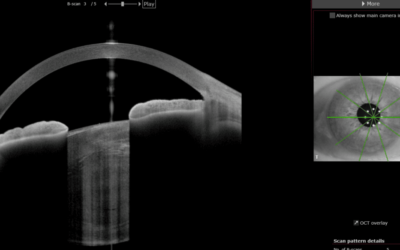

Sistema que estima de un modo virtual mediante imágenes Scheimpflug el grado de transparencia del cristalino, cristal transparente que se va opacificando por diversas causas dando como consecuencia la llamada catarata.